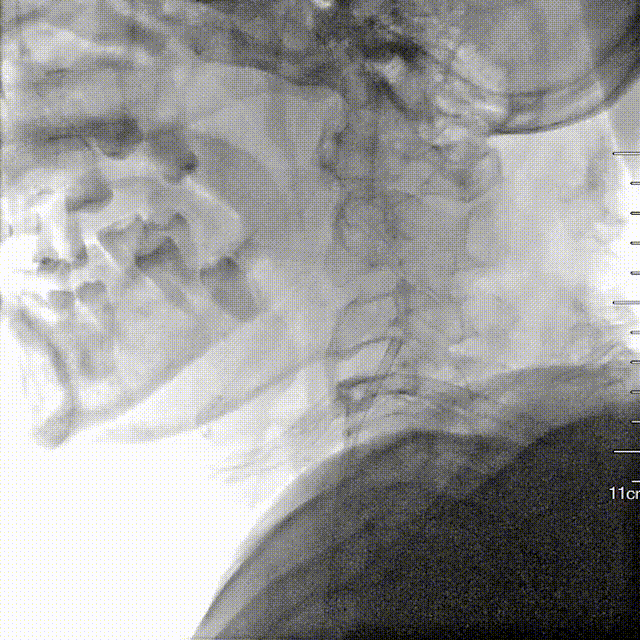

反复尝试经股动脉入路推进NeuronMax失败。

Esperance®抽吸导管推进至基底动脉闭塞处。

使用Esperance®抽吸导管在基底动脉进行ADAPT技术操作,达到mTICI 3级血流再通。